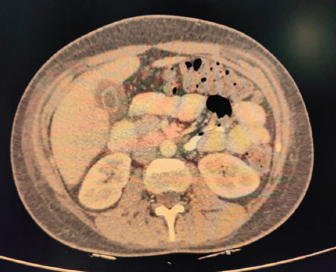

USG’s whole abdomen revealed hepatomegaly and mild to moderate ascites. In view of melena and thrombocytopenia, 6 units of random donor platelets were transfused. A workup for fever with thrombocytopenia and polyserositis was started. Dengue RTPCR, NS1 antigen, IgM, Weil felix, and VDRL were negative. Viral markers (HIV/HBsAg/Anti HCV/Anti HAV IgM/Anti HEV IgM) were negative. Scrub IgM, Brucella IgM, Urinary legionella antigen, CMV PCR, and Leptospira IgM were negative. Malaria Ag and P/S for the malaria parasite were negative. The widal test and Typhidot IgM were negative. CPK and CK-MB were negative. Stool occult blood (three samples) were negative. Covid PCR was negative. Blood and urine C/S were negative. Urine KOH revealed few budding yeast cells. Urine fungal culture was negative. Workup for EBV revealed 24,300 copies of EBV RTPCR and EBV IgM and IgG were positive. We did an autoimmune workup considering a young female with polyserositis but both ANA by Immunofluorescence and ANA profile were negative. Direct and indirect Coombs tests were negative. By the end of first week of admission, thrombocytopenia started improving but she had a persistent cough and fever although spikes were reduced. A 2D echo revealed trace pericardial effusion. Repeat Chest X-ray revealed persistent bilateral pleural effusion (Right > Left) (Fig. 2). In view of persistent effusion, we decided to perform a CECT chest and abdomen which revealed evidence of moderate right pleural effusion, minimal fluid in the left pleural cavity with atelectatic changes in the adjacent lung, oedematous thickened gallbladder and mild ascites (Figs. 3 and 4).

Fig. 2. Repeat chest X-ray showing persistent bilateral pleural effusion (Right > Left).